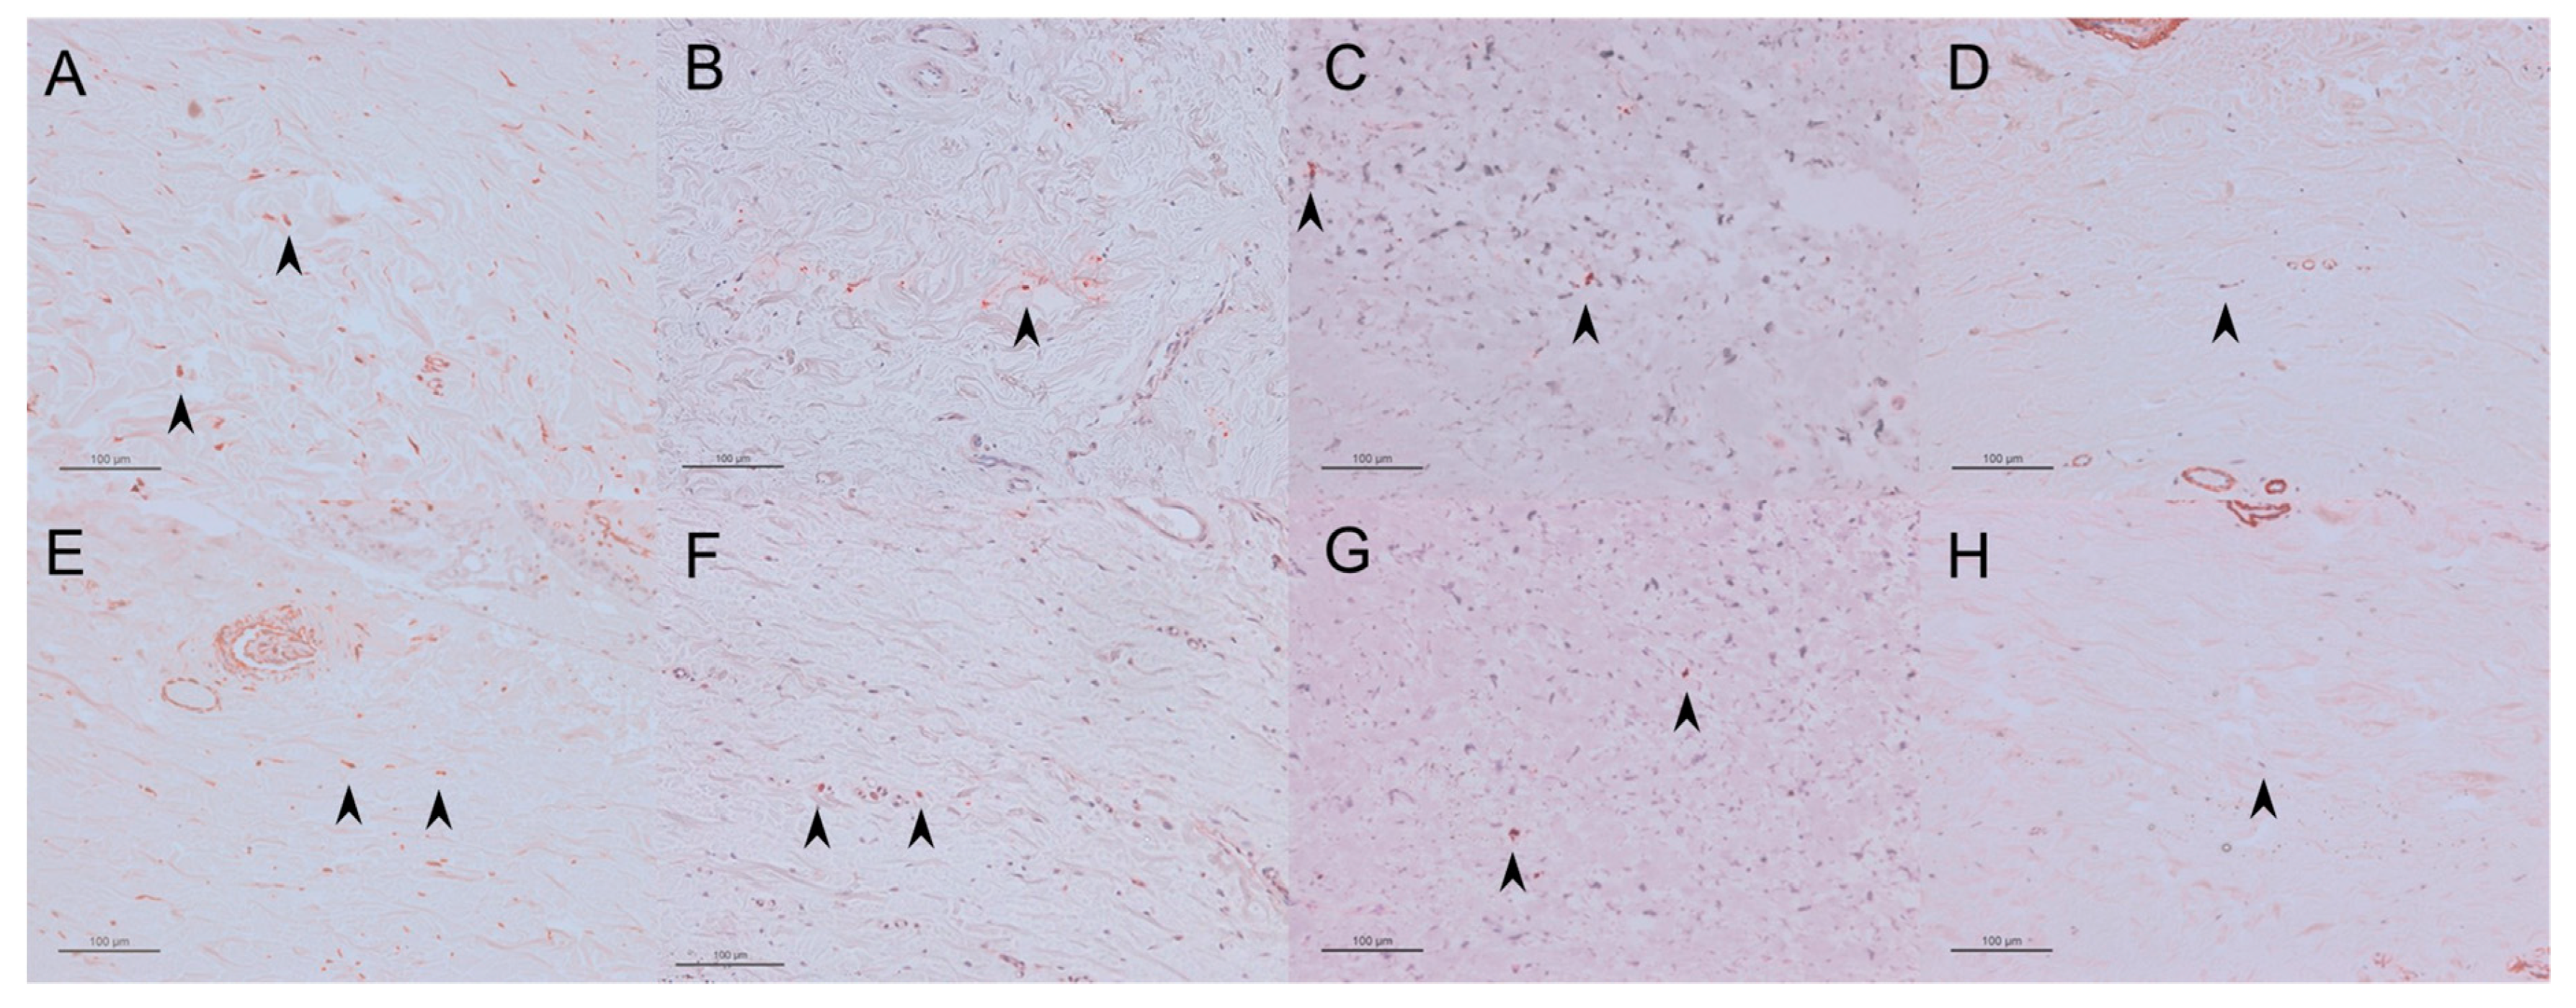

A lower number of vimentin-, TGF-β-, PCNA-, and αSMA-positive cells were found in the regorafenib group than in the control group (Figure 4, Table 1).

Figure 4.

Representative immunohistochemical staining images of the sections for vimentin-positive cells in the control group (A) and the regorafenib group (E), for TGF-β-positive cells in the control group (B) and the regorafenib group (F), for PCNA-positive cells in the control group (C) and the regorafenib group (G), and for αSMA-positive cells in the control group (D) and the regorafenib group (H). Cells are indicated by black arrows. Scale bars: 50 μm.

There was no significant difference in the numbers of these cells between the two groups (Figure 9, Table 2).

Figure 9.

Representative immunohistochemical staining images of the section for vimentin-positive cells in the MMC group (A) and the regorafenib group (E), for TGF-β-positive cells in the MMC group (B) and the regorafenib group (F), for PCNA-positive cells in the MMC group (C) and the regorafenib group (G), and for αSMA-positive cells in the MMC group (D) and the regorafenib group (H). Cells are indicated by black arrows. Scale bars: 100 μm.